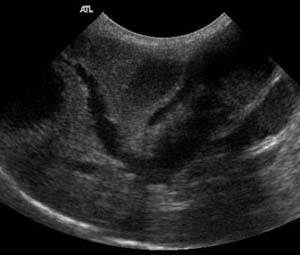

Для иследования печени, поджелудочной железы и желчного пузыря также могут быть использованы рентген брюшной полости и УЗИ. В некоторых случаях, когда лабораторные анализы и другие методы не помогают при диагностике, может потребоваться диагностическая операция – лапаратомия. Диагностическая лапаратомия также имеет преимущество одновременного исправления проблемы, если она будет найдена в процессе исследования.